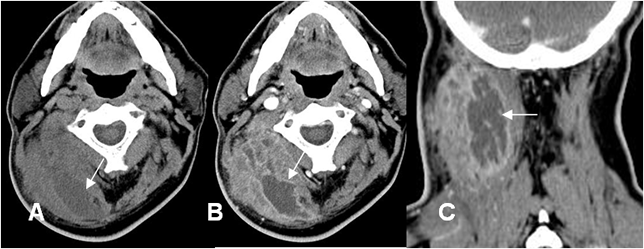

Fig 20. Absceso.

A: TAC axial simple, B: TAC axial con contraste y C: TAC reconstrucción coronal con contraste. Prominencia de los tejidos blandos en la región posterolateral derecha del cuello, con pérdida de los planos grasos entre los grupos musculares. Con el contraste se identifica imagen ovalada e hipodensa cuyos bordes captan y que corresponde a absceso.